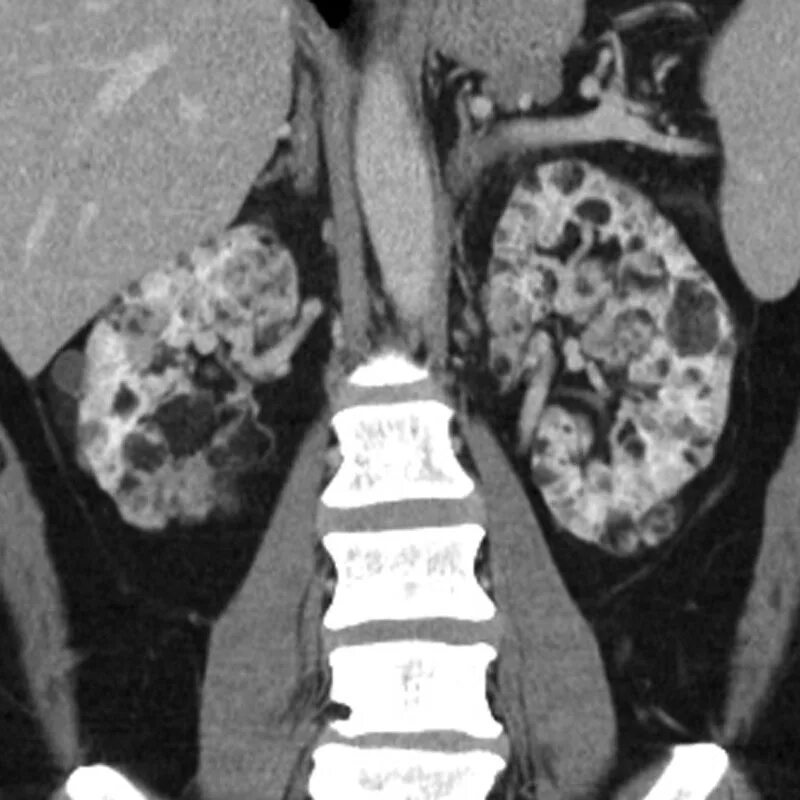

Туберкулезный склероз